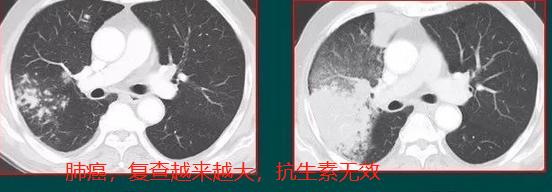

抗炎治疗无效,病灶逐渐增大,肺癌

分叶状肿块,支气管截断,周围没有云雾状影,病理为大细胞癌